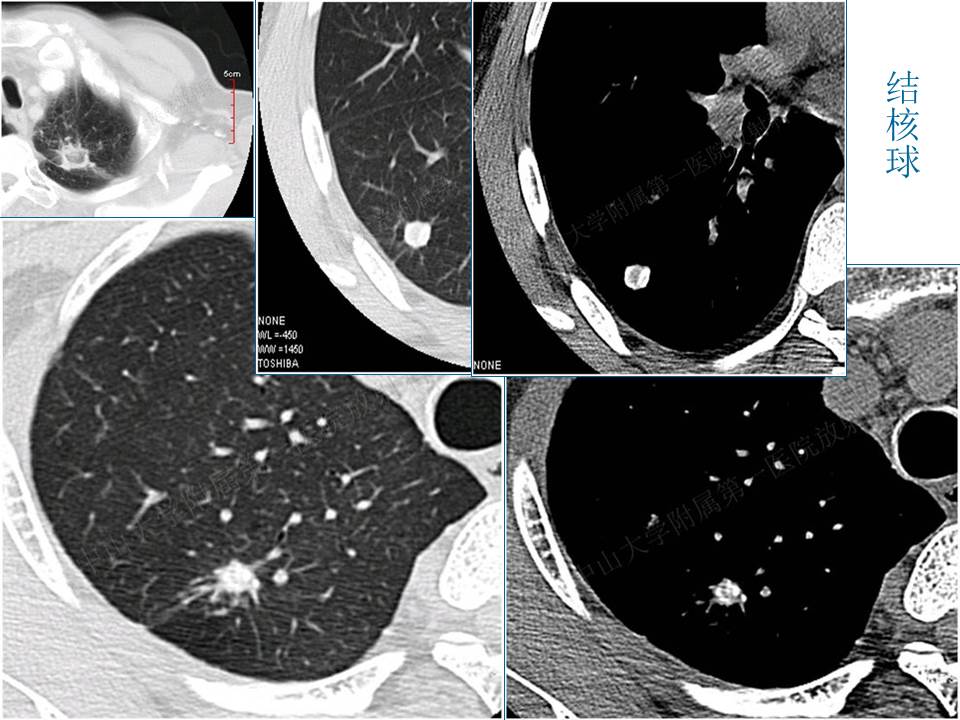

支气管肺癌的影像学诊断